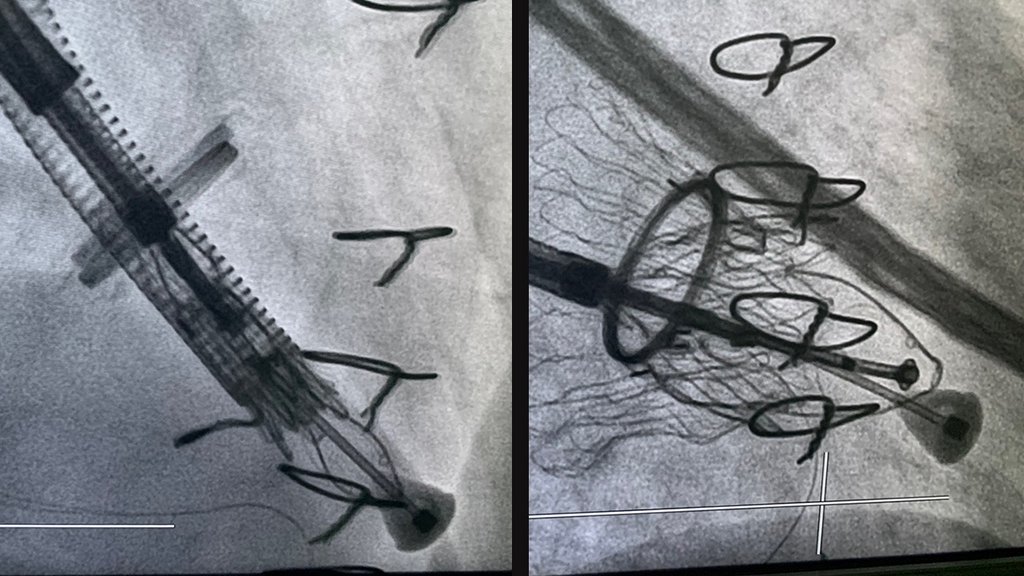

A novidade da técnica empregada no Hospital Vithas Vigo é a intervención percutánea, é dicir, a través dun implante dunha válvula biolóxica con técnicas de transcateter. A través da vea iugular dereita, no pescozo, introdúcense uns catéteres a través dos que se despraza a válvula encartada ata que está na posición correcta. Unha vez na posición axeitada, libérase a válvula, que se expande por un mecanismo de autoexpansión e ancórase á parede dereita do tabique intraventricular. Desta forma, a válvula comeza a funcionar correctamente e evita o refluxo se sangue do ventrículo á aurícula, e mellora a circulación do sangue cara á arteria pulmonar.

Neste sentido, o Dr. Íñiguez pon en valor a necesidade e calidade das imaxes de ecocardiografía tridimensional intraoperatorias que permiten realizar este tipo de procedementos con garantía en tempo real, xunto á gran profesionalidade dos facultativos da unidade de cardioloxía intervencionista que realizaron a intervención e dos coidados pre e postoperatorios por parte dos cardiólogos clínicos, “que posibilitaron non só unha intervención con éxito, senón unha evolución postoperatoria sen complicacións en tempo récord”.